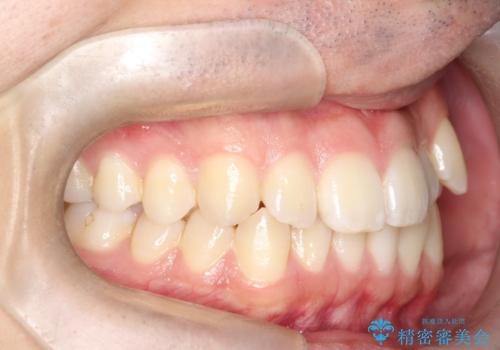

- 八重歯が気になるとのことでご来院されました。お口の中を確認すると、上の前歯がスペース不足で押し出され、少し前に出ている状態でした。抜歯せずに整えるため、奥歯を少しずつ後ろに動かしながら(遠心移動)、歯と歯の間をわずかに削るIPRを行ってスペースを作ることにしました。また、上下の噛み合わせを整えるために2級ゴム(エラスティック)を使用する方針を立てました。

マウスピースを段階的に交換しながら、奥歯を少しずつ後ろへ動かし、八重歯がきれいに並ぶよう調整しました。前歯の突出感を抑えるためにIPRを行い、スムーズに配列。さらに、2級ゴムを活用して噛み合わせも改善しました。治療後は、自然な歯並びになり、笑顔に自信が持てるようになったと喜んでいただきました。